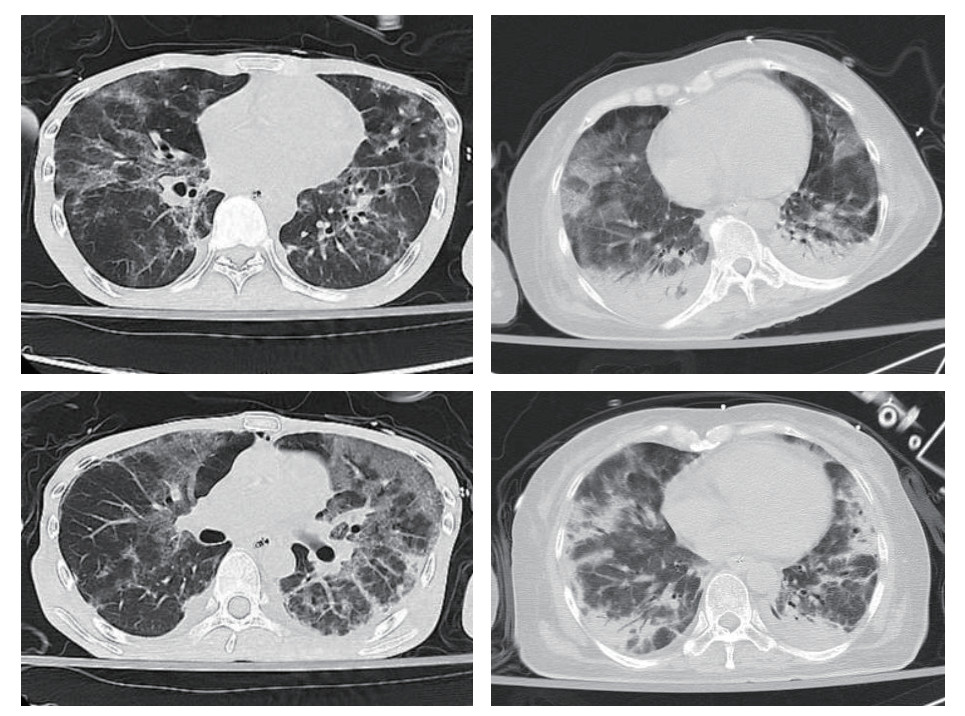

2 结果 2.1 基本情况比较本研究初步纳入50例PCP确诊病例,其中排除4例HIV阳性病例,最终有46例HIVn-PCP病例纳入研究。其中男性24例(52.00%),女性22例(48.00%),年龄(56.43±14.47)岁,总病死率为47.83%(22/46)。大部分患者都有长期应用皮质激素(25/46,54.35%)、应用免疫抑制剂(13/46,28.26%)或放化疗(16/46,34.78%)等病史。主要临床表现为呼吸困难(40/46, 86.96%),发热(39/46,84.78%),咳嗽和(或)咳痰(29/46, 63.04%),胸部影像学表现均有磨玻璃影(46/46, 100%,图 1),其次为胸腔积液(20/46, 43.48%)及肺实变(9/46, 19.57%)。

| 图 1 HIVn-PCP患者胸部CT:两肺多发斑片影及磨玻璃影,两下肺实变 |